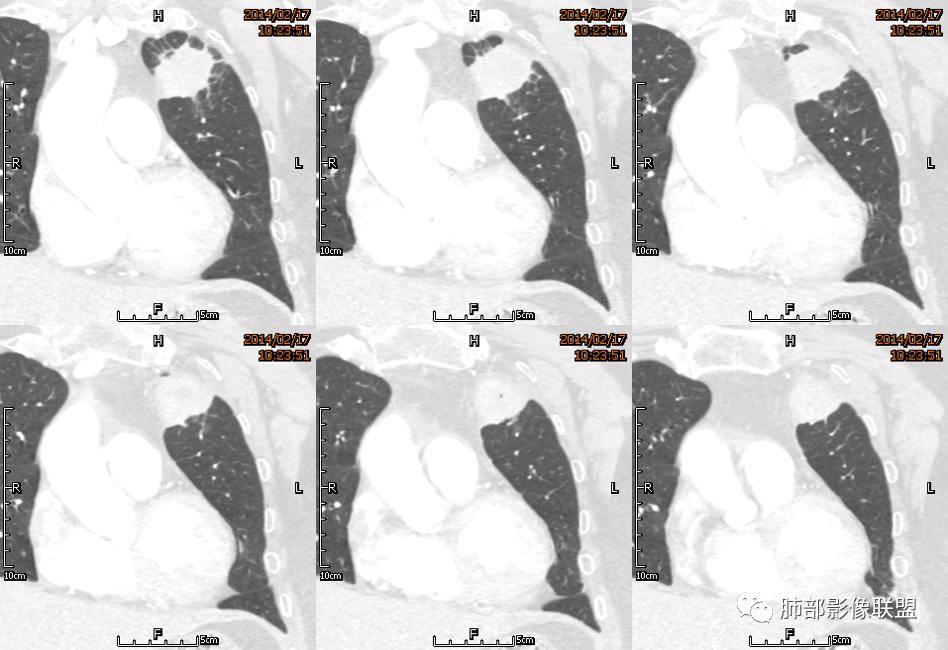

红星: 老年女性,咳嗽咳痰10天,痰中带血4天。左肺上叶前段胸膜下肿块影,沿支气管方向走行以膨胀生长为主,局部有收缩改变,支气管血管绝断,中间有小片状的坏死及小的空洞影,增强扫描病灶明显的强化,病灶周围网格状的小叶间隔增厚。拟左肺上叶前段浸润型腺癌并癌性淋巴管炎。鉴别诊断结核肉芽肿。

傅昌瑜: 老年女性,咳嗽咳痰10天,痰中带血4天。左肺上叶前段胸膜下肿块影,沿支气管方向走行,膨胀生长为主,局部边缘似有收缩改变,中间有小片状的坏死,支气管进入,增强扫描病灶明显的强化,血管走形较自然(血管漂浮征?),病灶周围网格状的小叶间隔增厚。考虑淋巴瘤可能性大,注意鉴别炎性肉芽肿及肺腺癌。

水晶石头: 患者老年女性,咳嗽咳痰10天,痰中带血4天余。查血常规白细胞低;肿瘤标志物、凝血功能正常;血生化:蛋白低;C反应蛋白、血沉稍升高。胸部CT:左肺上叶前段胸膜下沿气管支气管走形肿块影,长轴与胸膜平行,见分叶、毛刺、支气管截断、空泡征象。增强明显强化,且见血管造影征及病灶内小灶低密度坏死区。左肺上叶尖后段见一结节灶。综合考虑恶性病变可能大,腺癌或淋巴瘤可能。鉴别诊断肺脓肿。

尘缘: 老年女性,咳嗽咳痰10天,痰中带血4天,白细胞及中性粒明显减低,轻度贫血。影像表现:左上叶肿块,边缘膨隆,局部平直,支气管稍扩张,进入后远端堵塞,内见小空洞及不规则坏死区,增强后强化明显,坏死边界较清,并见环状强化区,内部血管走行自然,周围见小叶间隔增厚呈大网格征。初步诊断:慢性炎性伴脓肿形成及肉芽组织增生。鉴别淋巴瘤及腺癌,先抗炎治疗后复查或直接穿刺明确。

2.左肺上叶前段胸膜下块状影,不规则呈“逗点样”延向肺门区,边界清楚,未见分叶、毛刺及张力,表面不规则棘突,状如“火焰”或“日冕”。相邻胸膜增厚,未见栽赃、卫星病灶。

3.病灶密度不均,中央坏死液化并见气泡影,支气管及血管贴边进入,较均匀环形强化(显示多层结构),未见明确壁结节。